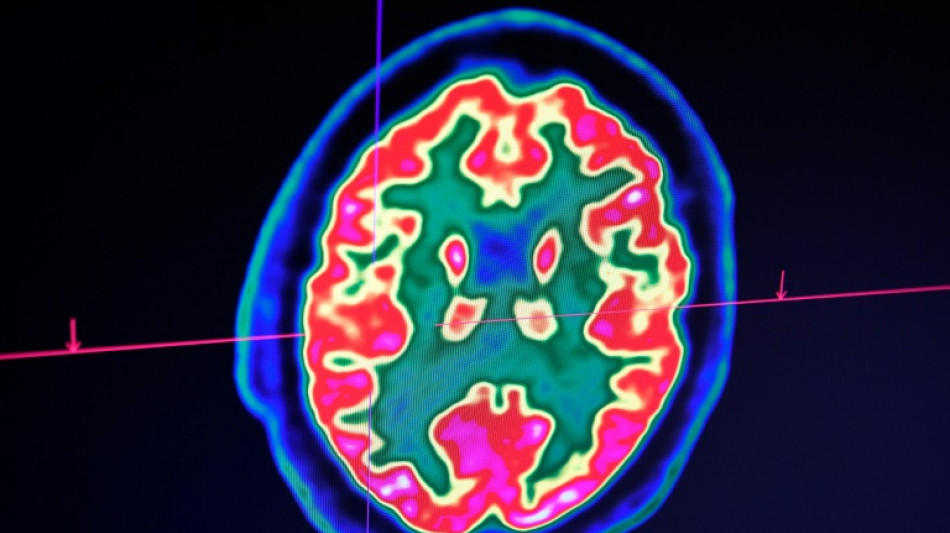

Sclérose en plaques: la découverte d'un lien avec un virus fait espérer une meilleure riposte

Sclérose en plaques: la découverte d'un lien avec un virus fait espérer une meilleure riposte / Photo: Fred TANNEAU - AFP/Archives

La découverte récente d'un lien entre la sclérose en plaques et le virus d'Epstein-Barr fait espérer une meilleure riposte à terme face à cette maladie, soulignent des spécialistes de la sclérose en plaques avant la journée mondiale de cette maladie, lundi.

Celle-ci est une maladie auto-immune du système nerveux central (cerveau et moelle épinière). Elle provoque un dérèglement du système immunitaire, qui s'attaque à la myéline, la gaine protectrice des fibres nerveuses.